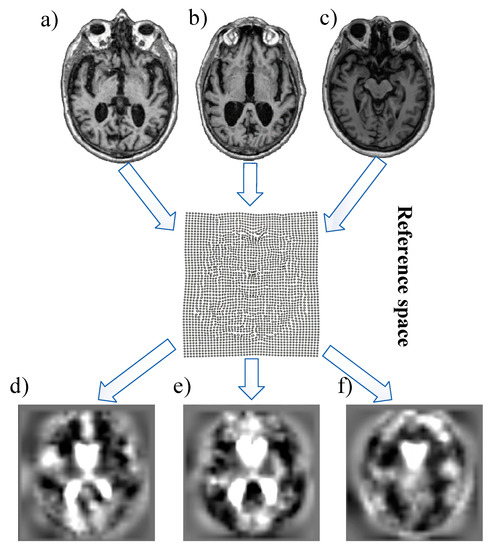

- Considering that morphometric images tend to yield more successful outcomes in disease diagnosis compared to raw or semi-processed MRI images, DL-based methods are employed for automatic feature extraction in the analysis of TBM images.

3.1. Tensor-Based Morphometry

- It can precisely and quantitatively measure the shape and size properties of brain structures with TBM.

- It can compress and reduce the data volume in brain images. This can help with faster data processing.

- It can be used to compare structural changes between different individuals, groups, or time points.

- TBM has the ability to make statistical analyses of brain structures.